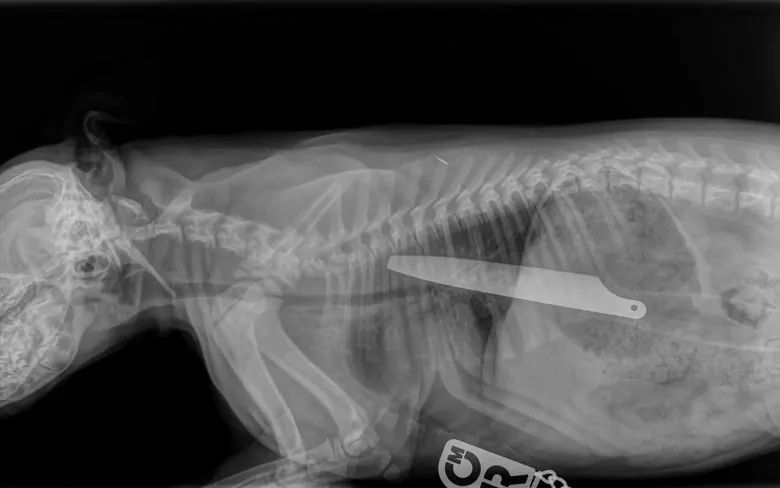

W brzuchu czworonoga tkwił niecodzienny i bardzo niebezpieczny przedmiot – nóż kuchenny.

Lekarz niezwłocznie wykonał zdjęcie rentgenowskie, które ponad wszelką wątpliwość pokazało, że w małym ciałku szczeniaka tkwi wyjątkowo niebezpieczny przedmiot, 20-centymetrowy nóż! W jaki sposób psiak dostał się do niego, pozostało zagadką, bowiem nikt z domowników tego momentu nie zauważył. Prawdopodobnie maluch, nieświadomy zagrożenia, capnął nóż z otwartej zmywarki.

Na swoje szczęście pies połknął nóż od strony rękojeści. Rączka noża tkwiła częściowo w jelitach i w brzuchu, ostrze zaś pozostało w przełyku. Nietrudno sobie wyobrazić, jak katastrofalne skutki wywołałoby połknięcie noża z odwrotnej strony.

Macie miała wyjątkowo dużo szczęścia, że przeżyła. Gdyby połknęła nóż od strony ostrza, niewątpliwie doszłoby do przebicia jej organów wewnętrznych.